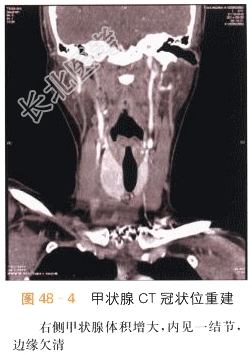

本案例CT扫描见右侧甲状腺增大,结节与正常甲状腺分界不清,呈低密度,见沙砾样钙化(见图48-1),增强后呈低度强化,甲状腺包膜不完整,(见图48-2~图48-4),结合超声检查,考虑甲状腺癌。